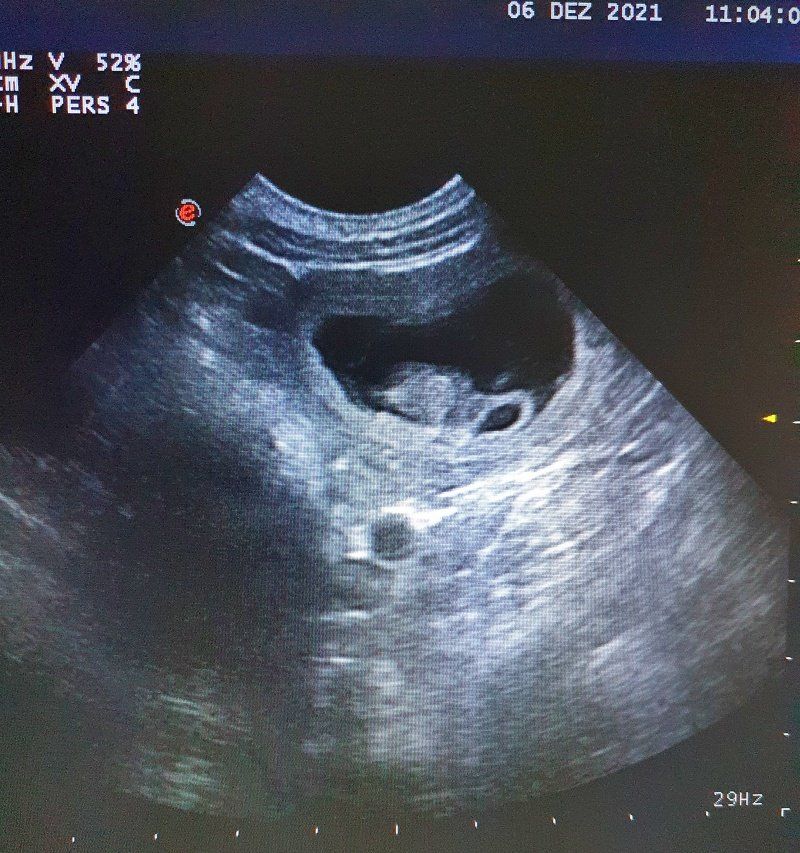

29 Tage später der spannende Tag

Das Ultraschall zaubert unseren Traum in die Wirklichkeit...kleine Miniminipudel mit kleinen Miniminiherzchen, die schon kräftig schlagen. Unsere Kelly wird wieder Mama und wir sind dankbar, glücklich und voller Vorfreude.